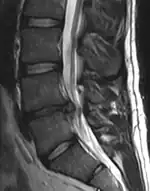

A herniated disc as seen on MRI, one possible cause of low back pain

The straight leg raise test can detect pain originating from a herniated disc. When warranted, imaging such as MRI can provide clear detail about disc related causes of back pain (L4–L5 disc herniation shown)